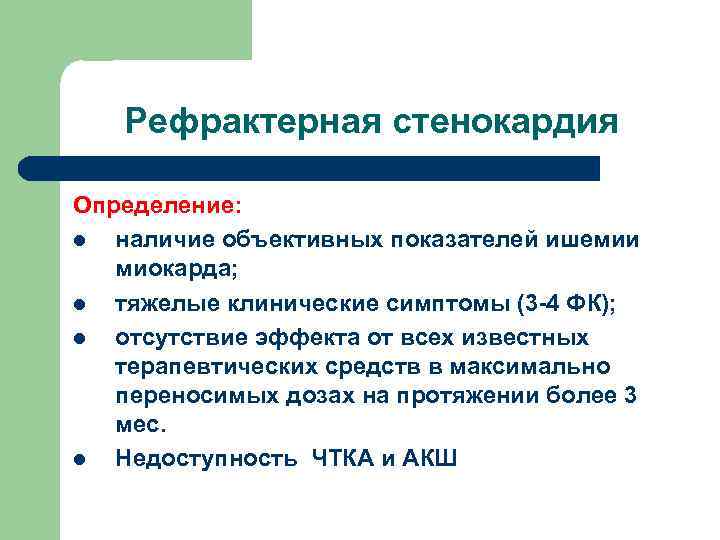

Рефрактерная стенокардия l l l Обычно соответствует III-IV ФК (ССS). Отсутствие эффекта от полноценной медикаментозной терапии. Противопоказана или затруднена хирургическая реваскуляризация.

Рефрактерная стенокардия Определение: l наличие объективных показателей ишемии миокарда; l тяжелые клинические симптомы (3 -4 ФК); l отсутствие эффекта от всех известных терапевтических средств в максимально переносимых дозах на протяжении более 3 мес. l Недоступность ЧТКА и АКШ